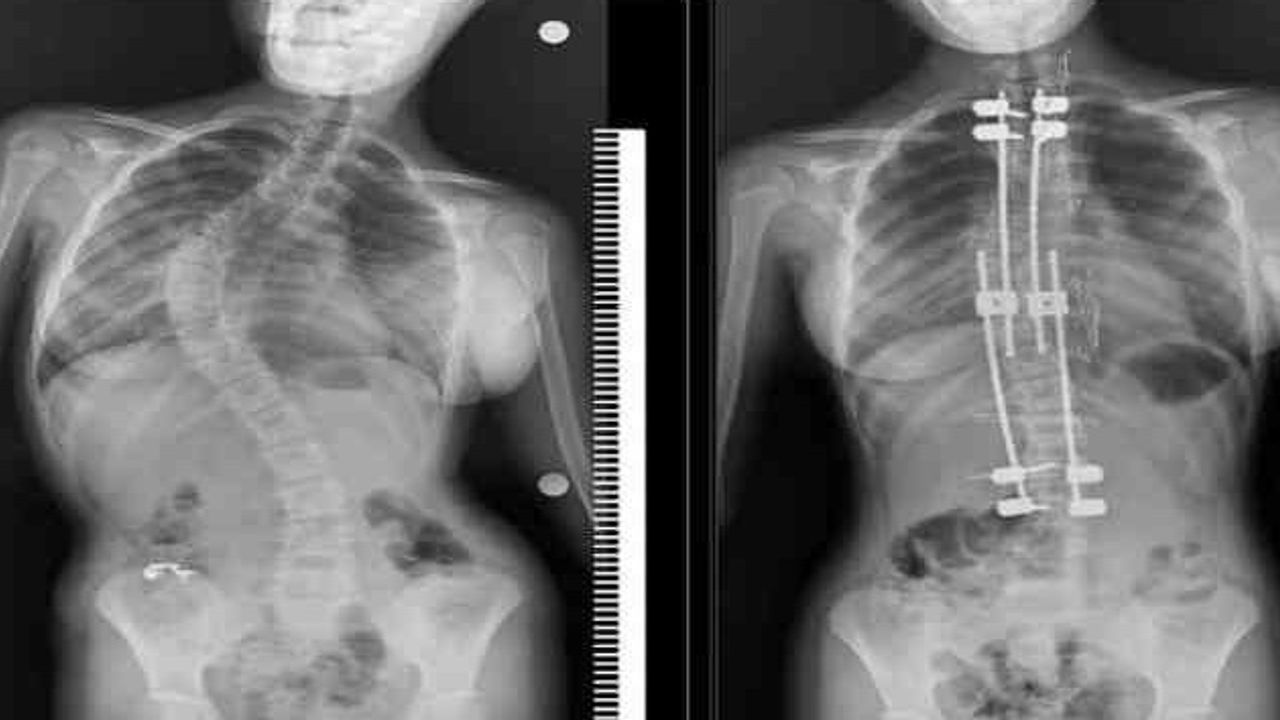

Skolyoz tanısının mutlaka bir uzman tarafından konulması gerektiğini belirten Bozkurt, "Önce fizik muayene yapılır, ardından skolyoz grafisi ile eğrilik derecesi ölçülür. Cobb açısı tedavi planının belirlenmesinde en önemli rehberdir" dedi.

"20 derece altı: Kişiye özel egzersiz ve postür eğitimi yeterli olur. 20-40 derece: Egzersizle birlikte skolyoz korsesi önerilir. 40-50 derece: "Gri alan" olarak kabul edilir, hastanın yaşına göre cerrahi kararı verilir. 50 derece üzeri: Genellikle cerrahi tedavi gerekir."